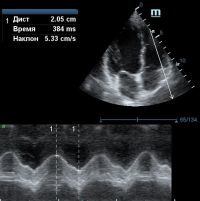

TAPSE - показатель амплитуды движения латеральной части кольца трикуспидального клапана, позволяет количественно и быстро оценить систолическую функцию правого желудочка, норма которого составляет более 17 мм. Главным условием является проведение линии М-режима параллельно стенке правого желудочка в апикальном четырех камерном сечении, что легко достигается при Free Xros.